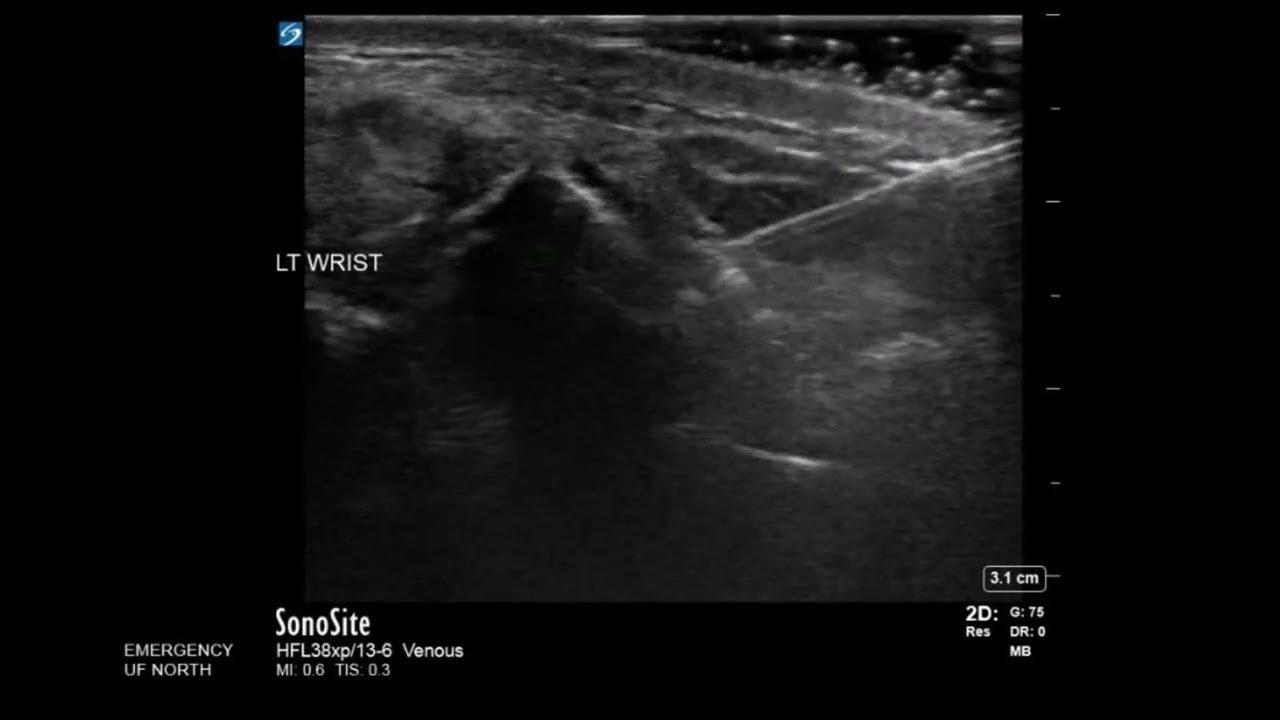

From www.youtube.com

Ultrasound Guidance In Hematoma Block YouTube How To Do Hematoma Block the hematoma block is a technique to inject a local anesthetic solution into the hematoma between the fractured bone. the hematoma block is a technique to inject a local anesthetic solution into the hematoma between the fractured bone. learn how to perform a hematoma block for closed reduction of a fracture. hematoma block is commonly used. How To Do Hematoma Block.

Wrist Ultrasound Distal Radius Fracture Hematoma Block YouTube How To Do Hematoma Block Apurv mehra demonstrate hematoma block. Find out what you need, where to inject, and how to avoid common mistakes. in this video dr. the hematoma block is a technique to inject a local anesthetic solution into the hematoma between the fractured bone. A hematoma block is based on. the hematoma block is a technique to inject a. How To Do Hematoma Block.